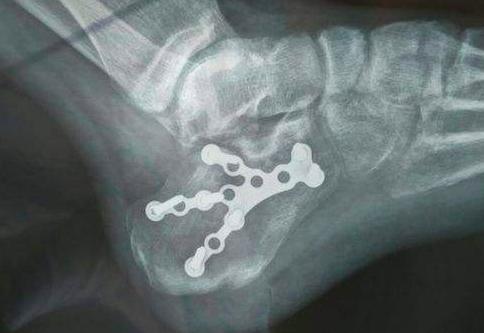

骨折严重者,需要经过手术钢板固定,将碎成几块的骨头,『拼合』起来固定。跟骨骨折的复位要求较高,要恢复关节与各关节面间的正常解剖关系(就是各归各位,保持正确的间距),同时,满足负重力线的种种要求。这样才能最大限度地减少创伤性关节炎的发生。

有点像把摔碎的鸡蛋壳,给缝起来。